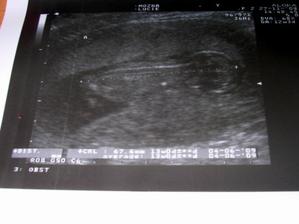

18.září jsme byli na našem 1.IVF... a 8.den od ET se mi "zjevily" nádherné // 🙂... přeju si,aby se všechno vyvíjelo dobře... 29.9 11.den po ET mi pro zhoršení OHSS provedli punkci Douglasova prostoru a odsáli 2 litry žlutého ascitu ☹ Nicméně se mi ulevilo 🙂 HCG ten den 259... 6.10 kontrola HCG - 2950 (18.den od ET)... 10.10 UTZ - čekáme DVOJČÁTKA 🙂 🙂 🙂... 17.10 krvácení a následná hospitalizace, UTZ - dvojčátkům bijí srdíčka, 20.10 HCG - 56000, 25.10 propuštění z nemocnice... 31.10 poslední kontrola v CARu, dvojčátka mají 2 a 2,1 cm... 11.11 UTZ - dvojčátka mají 3 cm... 24.11 UTZ - dvojčátka mají 9 cm (ale moc se mi to měření nezdá, ve čtvrtek na screeningu se ukáže pravda, čeká nás 3D 🙂) 27.11 screening I.trimestru - miminka jsou zdravá, od hlavičky po prdelku mají 7 cm... 19.12 3D - miminko "A" je chlapeček, "béčko" chce zůstat zatím v utajení 🙂 tak snad příště 🙂... 8.1 3D - miminko "B" je holčička 🙂 19.1 echokardiografie - obě srdíčka jsou zdravá 🙂 20.1 screening II.trimestru - vše OK, miminka mají 360 a 364 gramů 🙂 26.1 UTZ - chlapečkovi se ztratil pindík a najednou čekáme 2 holčičky 🙂) Doufám, že už je to definitivní 🙂) 19.2 UTZ 3D4 - holčičky potvrzeny!!! 🙂 mají každá téměř 800 gramů! 🙂 20.3 UTZ - holčičky mají 1700 a 1800 gramů! 8.4 UTZ - holky mají neuvěřitelné váhy 2415 a 2600 gramů! 11.5 nástup do nemocnice... 11.května ve 20,03 se nám akutním císařským řezem narodila Eliška (2970/48) a o minutu později Nelinka (3200/50).Jsme nejšťastnější rodiče na světě! 🙂